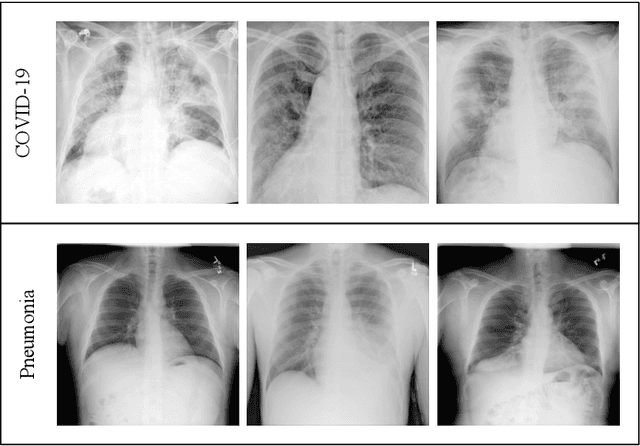

Abstract:With the ever increasing demand for screening millions of prospective "novel coronavirus" or COVID-19 cases, and due to the emergence of high false negatives in the commonly used PCR tests, the necessity for probing an alternative simple screening mechanism of COVID-19 using radiological images (like chest X-Rays) assumes importance. In this scenario, machine learning (ML) and deep learning (DL) offer fast, automated, effective strategies to detect abnormalities and extract key features of the altered lung parenchyma, which may be related to specific signatures of the COVID-19 virus. However, the available COVID-19 datasets are inadequate to train deep neural networks. Therefore, we propose a new concept called domain extension transfer learning (DETL). We employ DETL, with pre-trained deep convolutional neural network, on a related large chest X-Ray dataset that is tuned for classifying between four classes viz. $normal$, $other\_disease$, $pneumonia$ and $Covid-19$. A 5-fold cross validation is performed to estimate the feasibility of using chest X-Rays to diagnose COVID-19. The initial results show promise, with the possibility of replication on bigger and more diverse data sets. The overall accuracy was measured as $95.3\% \pm 0.02$. In order to get an idea about the COVID-19 detection transparency, we employed the concept of Gradient Class Activation Map (Grad-CAM) for detecting the regions where the model paid more attention during the classification. This was found to strongly correlate with clinical findings, as validated by experts.